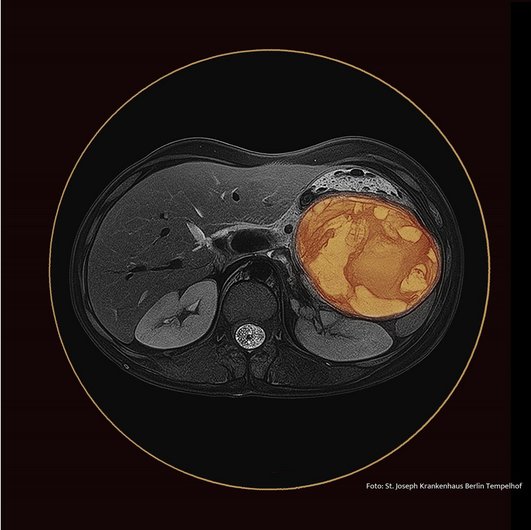

Die unser heutiges Infektoskop begleitende - mit allen Mitteln der Bildbearbeitung manipulierte - MRT ihres Abdomens zeigt eine ovaläre Raumforderung im linken Mittelbauch mit einem transversalen Durchmesser von 10 x 8 cm. Diese Läsion führt zu einer Verlagerung der Cauda des Pankreas nach kaudal. In der T2w-Sequenz ist sie signalinhomogen mit signalhyperintensen zentralen Anteilen und Septen. In der diffusionsgewichteten Bildgebung ist diese vornehmlich zentral diffusionsgestört. Wir zeigen die Bilder Herrn Tröger, dem Chefarzt für Gastroenterologie. Sein spontanes Urteil: „Das ist ein Frantz Tumor.“ Der Chefarzt der Radiologie, Herr Trübenbach, hat viel nachgedacht und auch er kommt zu dem Schluss, dass das Bild mit der Verdachtsdiagnose Frantz Tumor sehr gut vereinbar sei. Seine Differentialdiagnose „Abszess“ schätzt er als weniger wahrscheinlich ein. Beide werden recht behalten, aber ihr Verdacht wird die Geschichte nicht in ihrer Vollständigkeit umfassen, sonst wäre dies hier nur ein „Gastroskop“ und nicht auch ein „Infektoskop“.